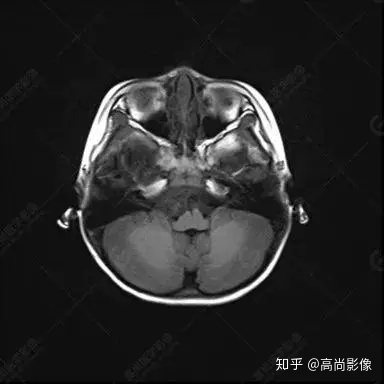

右側(cè)顳葉腫瘤切除術(shù)后(具體不詳):右側(cè)顳部骨質(zhì)不連續(xù)呈術(shù)后改變,右側(cè)顳葉術(shù)區(qū)見片狀長T1長T2信號(hào)影,F(xiàn)LAIR呈低信號(hào);術(shù)區(qū)后方右側(cè)顳枕葉見一巨大占位性病變影,邊界欠清,大小約6.2×5.8×4.3cm(前后×左右×上下),信號(hào)不均勻,T1WI呈等稍低信號(hào)間雜少許高信號(hào),T2WI呈高稍低混雜信號(hào),DWI示部分病灶彌散受限,相應(yīng)ADC圖減低,磁敏感序列見部分呈極低信號(hào),增強(qiáng)掃描可見明顯不均勻強(qiáng)化,鄰近硬腦膜及小腦幕增厚并明顯強(qiáng)化;另延髓右前方及右側(cè)橋小腦角區(qū)見一不規(guī)則形異常信號(hào)影,大小約3.2×1.3×3.7cm(左右×前后×上下),呈長T1稍長T2信號(hào),F(xiàn)LAIR呈等信號(hào),DWI未見受限,增強(qiáng)后明顯均勻強(qiáng)化,鄰近腦膜明顯強(qiáng)化。鄰近腦實(shí)質(zhì)及右側(cè)顳角明顯受壓;左側(cè)大腦半球未見局灶性信號(hào)異常,中線結(jié)構(gòu)稍左移。

右側(cè)顳葉腫瘤切除術(shù)后:現(xiàn)術(shù)區(qū)后方右側(cè)顳枕葉及延髓右前方占位,右側(cè)顳枕部硬腦膜及小腦幕明顯強(qiáng)化,結(jié)合既往影像資料,考慮為胚胎源性惡性腫瘤,如非典型畸胎樣/橫紋肌樣瘤(AT/RT)或原始神經(jīng)外胚層腫瘤(PNET)。